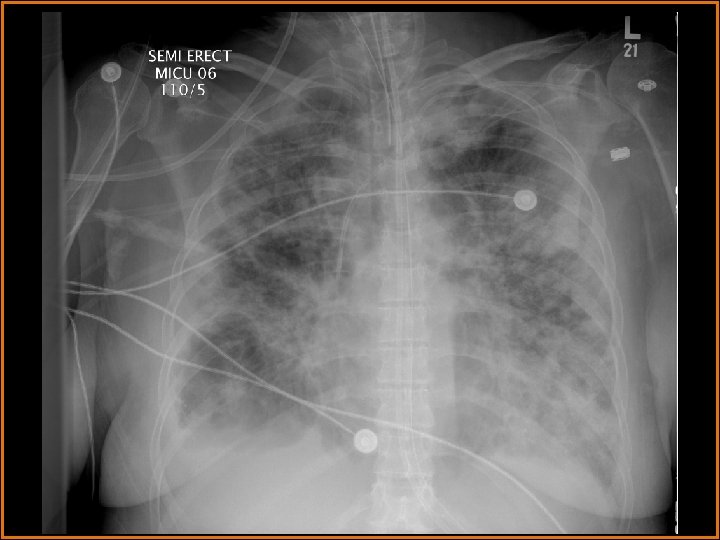

Case History 64 -year-old female presents with fever. Two serial portable chest radiographs are provided.

Findings and Differentials Chest x-ray findings: Multiple bilateral patchy alveolar opacities are seen diffusely. Many of these opacities are nodular, and some are cavitary. There are bilateral pleural effusions. Retrocardiac opacification is seen and may be secondary to the effusions and/or the airspace disease. The life support lines and tubes are unremarkable. A large lucency projects over the right hemidiaphragm. What would you like to do next? Think about your answer before advancing to the next slide.